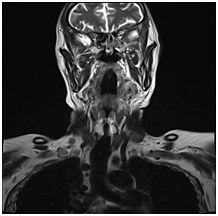

A 70 years old male patient presented to the emergency department with stridor and dysphagia of 3months duration. Patient was examined by fiber optic nasopharyngoscope which revealed supra-glottic mass to the left side with restricted mobility of the left vocal cord. Patient was admitted and submitted for urgent tracheostomy. MRI neck with contrast was done and revealed a Supraglottic mass measuring about 2cm X 1.5cm, partially occluding the airway and showing enhancement post gadolinium injection. It is appearing isointense in T1 and T2-weighted images with mildly enlarged vocal cords (Figure 1–3).  Panendoscopy was performed on 18/02/2018 and revealed a mass occupying the post cricoid area, pyriform fossa, supraglottic and the lateral pharyngeal wall. Base of the tongue, tonsils, right side of the larynx and the posterior pharyngeal wall were free.

Figure 3 MRI neck with contrast, coronal cut, showing mildly enlarged vocal cords.

Figure 7 MRI neck, coronal cut, showing the old postoperative changes with right hemi glossectomy.